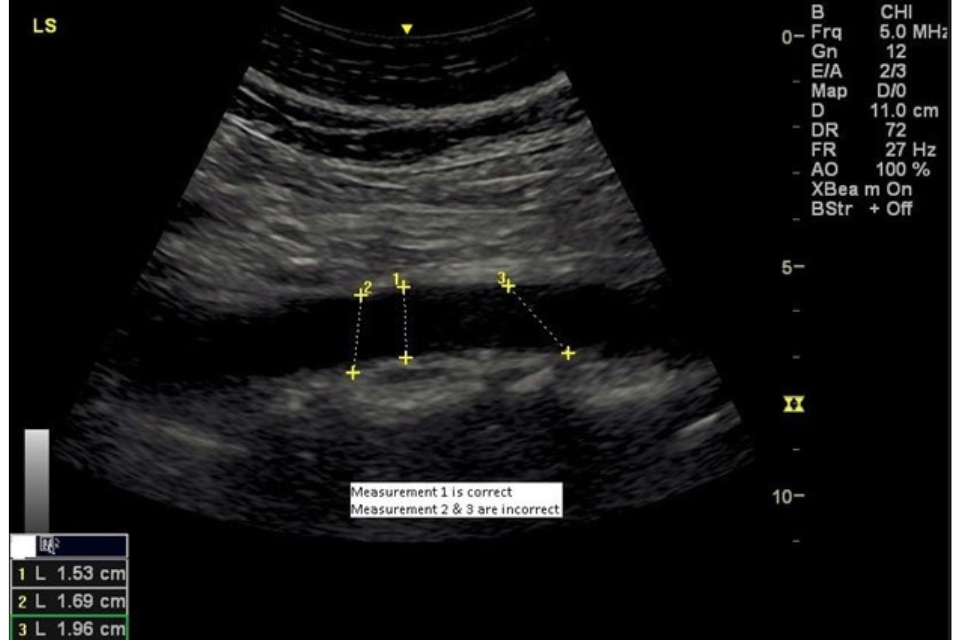

Figure 2. Measurement of the abdominal aorta showing the correct and incorrect lines of measurement

The maximum longitudinal (internal anterior wall to internal posterior wall) diameter of the aorta should be measured, and an image recorded and stored (figure 2). The image should demonstrate the lumbar spine. The images must be annotated to demonstrate the scan orientation.

The aorta should be measured at its maximum anterior posterior diameter in TP and LP ensuring that the line of measurement is perpendicular to the aortic lumen at the point of measurement and not taken in an oblique plane (figure 1).